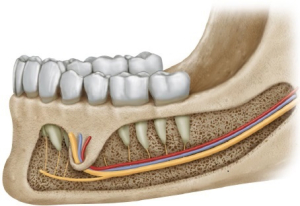

عصب آلوئولار تحتانی یکی از شاخههای اصلی عصب سهقلو (Trigeminal nerve) است که وظیفهی انتقال حس از دندانهای فک پایین، لب پایین، چانه و بخشی از لثهها را بر عهده دارد. این عصب از کانالی استخوانی در داخل فک پایین عبور میکند که به آن کانال مندیبولار گفته میشود.

نکتهی مهم این است که ریشههای دندان عقل پایین در بسیاری از افراد در تماس نزدیک یا حتی چسبیده به این کانال عصبی قرار دارند و همین موضوع، جراحی این دندان را به عملی حساس تبدیل میکند.

آسیب عصب فک پایین در زمان جراحی دندان عقل معمولاً به یکی از دلایل زیر اتفاق میافتد:

1. نزدیکی بیش از حد ریشه دندان عقل به عصب

در برخی بیماران، ریشههای دندان عقل:

- دور عصب پیچیدهاند

- به کانال عصبی فشار میآورند

- یا حتی از دو طرف عصب عبور کردهاند

در چنین شرایطی، خارج کردن دندان بدون خطر عصبی نیازمند مهارت و برنامهریزی دقیق است.

در قدم اول، عکس OPG میتواند نشانههایی از خطر را نشان دهد، مانند:

- تیره شدن ریشهها

- انحراف کانال عصبی

- قطع شدن دیوارهی کانال

در موارد مشکوک، تصویربرداری سهبعدی CBCT ضروری است. این روش:

- موقعیت دقیق عصب را مشخص میکند

- میزان تماس ریشه با عصب را نشان میدهد

- به جراح در انتخاب تکنیک مناسب کمک میکند